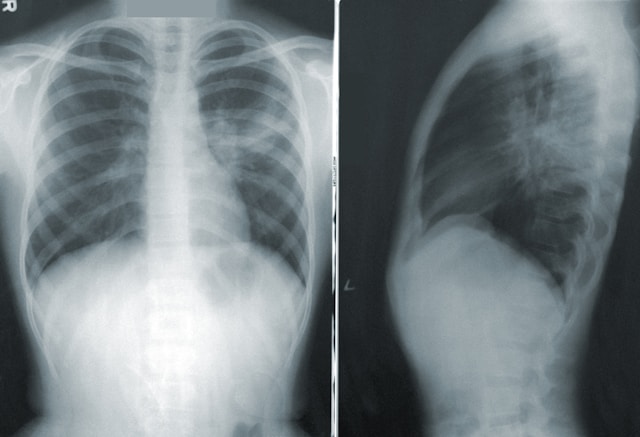

폐렴 사진

• 흉부 X선: 폐렴의 존재를 확인할 수 있습니다.